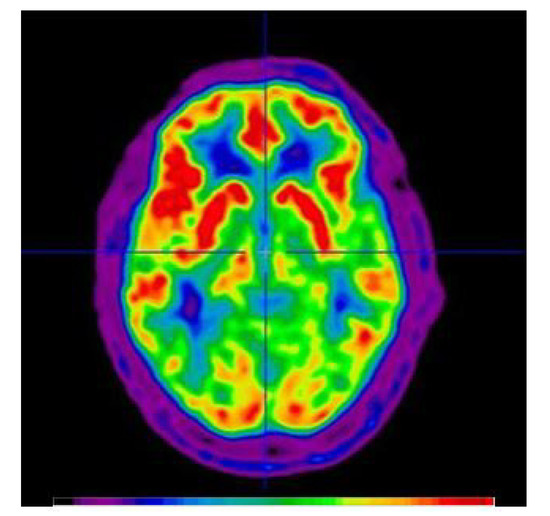

Figure 3.

An example of [15O]Water Positron Emission Tomography (PET). The image is scaled in activity units (kBq/cc). The image was created by summing the first 40 seconds immediately post-bolus transit from a dynamic imaging sequence initiated at the time of [15O]water injection. The image is a semi-quantitative representation of the cerebral blood flow (CBF) at the time of bolus arrival in the brain. The color bar describes increasing blood flow with increasing signal intensity (from black to red).